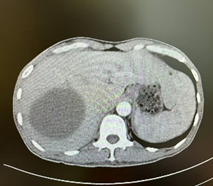

新辅助(两次HAIC和两个周期靶免治疗)后MR

由于病人一般情况较好,肝功能良好(Child-pugh A级),经多学科会诊临床确认肿瘤为IIb期肝细胞癌,属于可切除性肝癌,但存在高危复发因素,建议先行新辅助治疗后手术切除。经两次肝动脉关注化疗(HAIC)(奥沙利铂+5-Fu+亚叶酸钙方案)和两个周期的靶向免疫治疗(仑伐替尼+帕博利珠单抗方案),第二次介入造影是肿瘤血供不明显,第二次介入治疗4周后复查CT提示肿瘤缩小不明显但坏死征象明显,经MRI证实仍有少许血供,于是经多学科会诊后决定行前入路右半肝切除术。